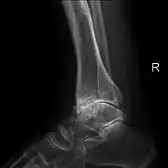

Diagnosis is made with reasonable certainty based on history and clinical examination.[42][43] X-rays may confirm the diagnosis. The typical changes seen on X-ray include: joint space narrowing, subchondral sclerosis (increased bone formation around the joint), subchondral cyst formation, and osteophytes.[44] Plain films may not correlate with the findings on physical examination or with the degree of pain.[45] Usually other imaging techniques are not necessary to clinically diagnose osteoarthritis.

Primary osteoarthritis of the left knee. Note the osteophytes, narrowing of the joint space (arrow), and increased subchondral bone density (arrow). -